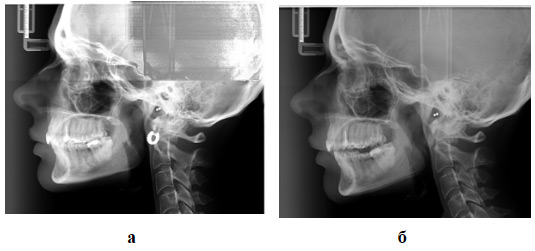

Проводилось рентгенологическое исследование — боковые ТРГ до начала лечения и через 3 месяца после его начала (Рис.4 а, б).

Рис.4. а — боковая телерентгенограмма до начала лечения, б — боковая телерентгенограмма с каппой спустя 3 месяца от начала лечения.

Сравнивались угловые и линейные показатели, которые описывают положение нижней челюсти в вертикальном и сагиттальном направлениях: Pm/Pb, s-n-spm, sna-me (Рис. 5, 6, 7).

По результатам анализа боковых ТРГ до лечения спустя 3 месяца от начала использования каппы, было установлено, что нижняя челюсть изменила свое пространственное положение по всем трем изучаемым параметрам в среднем на 6,2% от первоначальных показателей (Рис. 8).